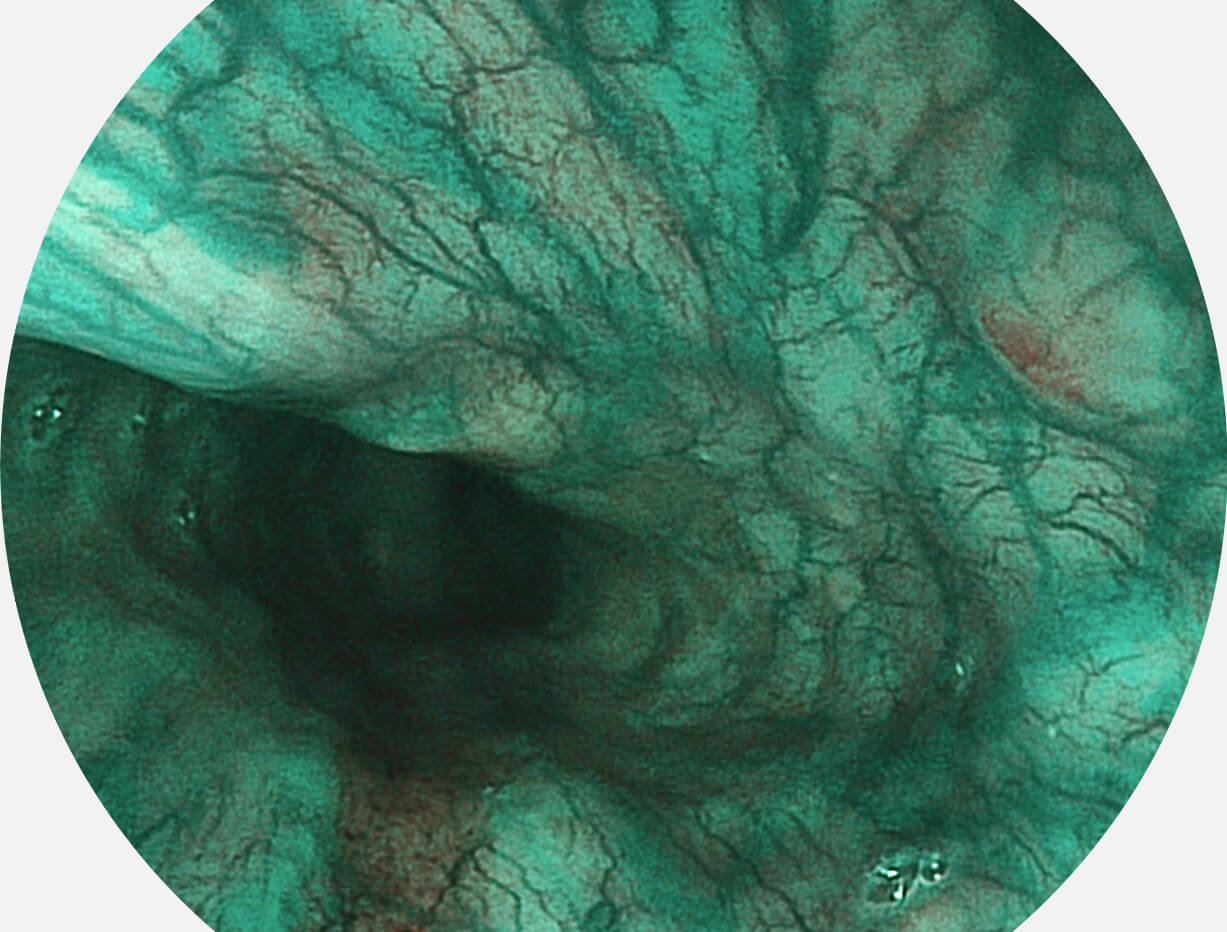

Spectral Focused lmaging, SFI

图像具有高亮度、高黏膜血管颜色对比度的特点,且不改变粘液、食物残渣、粪便的基本颜色,可在中远景下进行观察,助力消化道早期疾病的诊断。

SFI图像